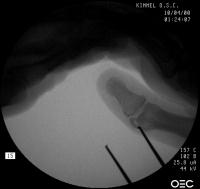

Intraoperative fluoroscopy. The mass:

Click for larger image